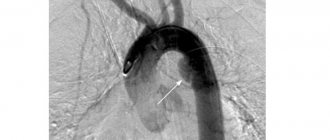

- Малоинвазивное эндоваскулярное лечение. Когда сосуды закупорены не полностью, чаще всего обходится без разрезов и общего наркоза: на помощь приходит эндоваскулярная хирургия. При заболеваниях артерий конечностей, связанных с нарушениями кровотока, применяется баллонная ангиопластика и стентирование. Проводится расширение просвета суженной артерии путем раздувания специального баллончика изнутри и установке в нее металлического стента, который играет роль каркаса, удерживающего стенки сосуда. Подробнее о том,как проходит стентирование сосудов ног, читайте тут.